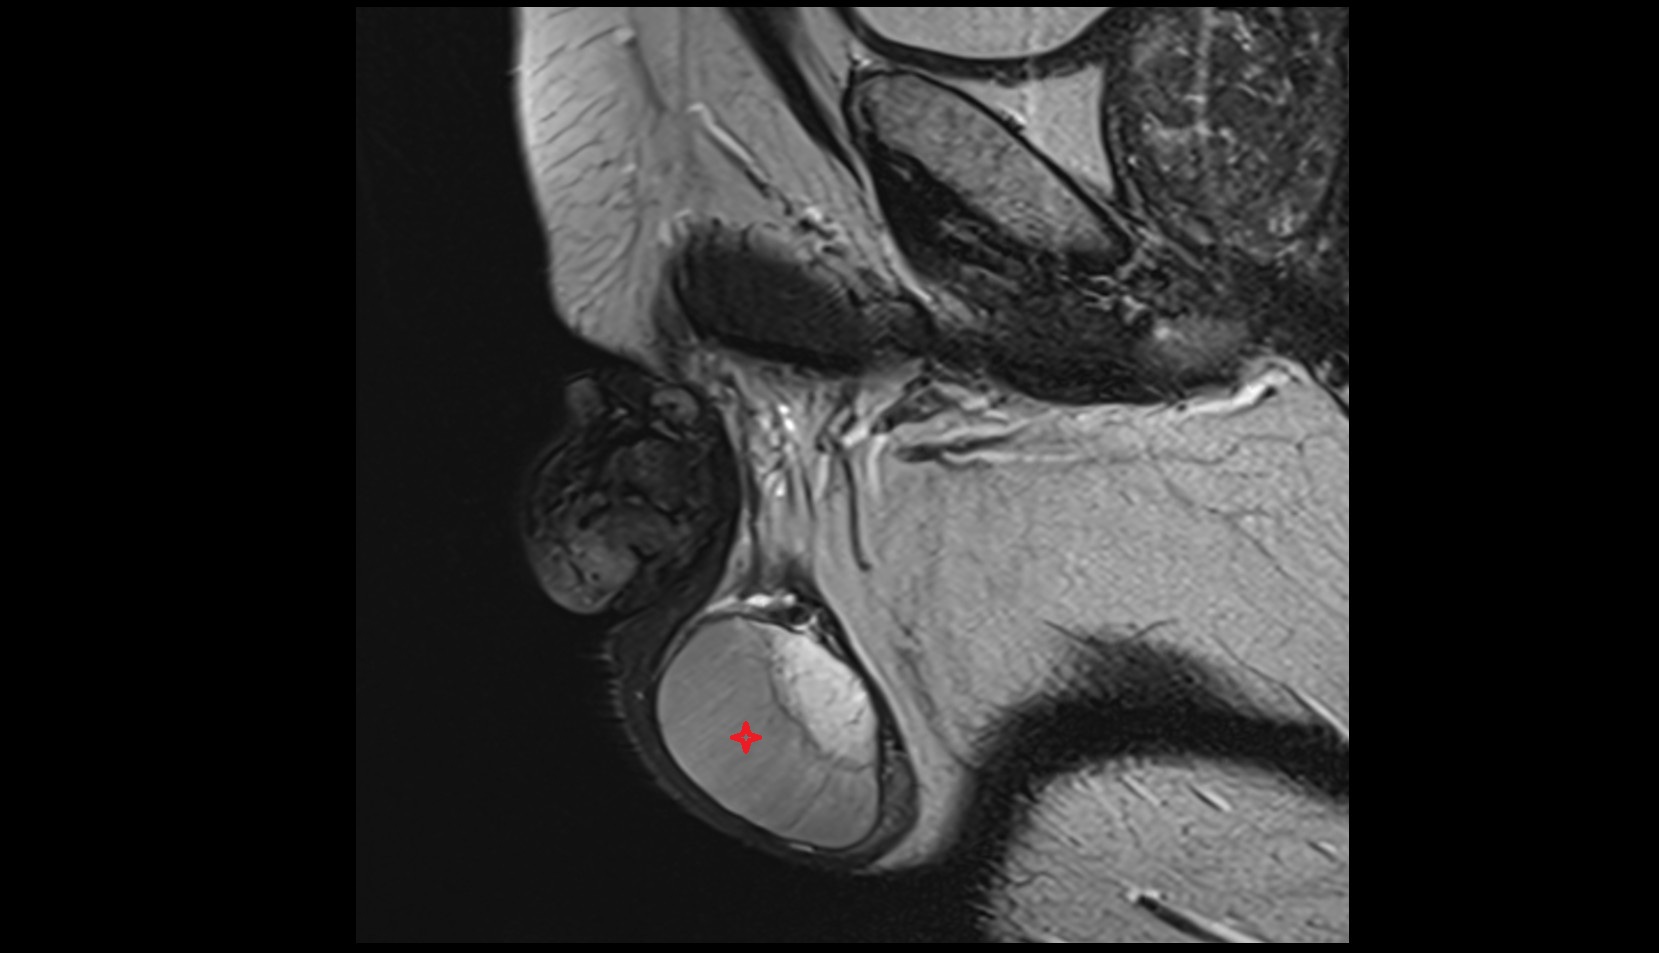

- Testis

- Head of epididymis

- Tail of epididymis

- Body of epididymis

- Epididymis

- Tunica albuginea of testis

- Parietal tunica vaginalis

- Lobule of testis

- Mediastinum testis

- Visceral tunica vaginalis

- Scrotal fluid

- Septum of testis